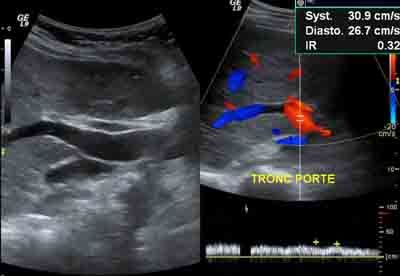

- les artères et les veines de l'abdomen

L'échographie n’utilise pas de rayons X. L’échographie utilise des ultrasons émis par une sonde et transmis dans les tissus qui les réfléchissent pour former une image de la région examinée. Elle peut être couplée à une sorte de radar pour l’étude des vaisseaux (doppler). Pour les intensités utilisées, il n’a jamais été décrit de conséquence particulière pour l’homme.